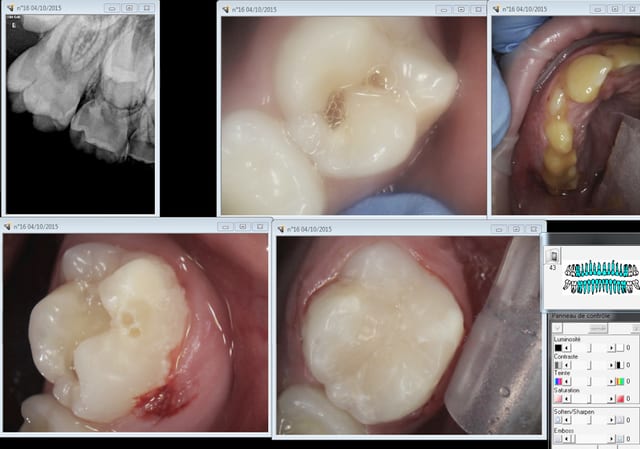

Cette fois ci c'est mon fils 9 ans. Ce petit con est laxiste et ne se lave pas assez les dents. Et ce qui devait arriver arriva : carie sur 16 ( la seule n'ayant pas eu droit à son sealant)

On a la désagréable impression de se retrouver à la fac, digue impossible à mettre, anesthésie moyenne et sensation qu'il reste toujours un peu de dentine ramollie et de faire une grosse merde. -))))

J'aurais du lui faire un amalgame étant stressé par une éventuelle contamination par la salive je me suis énervé au cours du soin c'était plus fort que moi, ce qui j'espère lui fera prendre conscience de la nécessité de mieux se brosser les dents.

Il a eu le droit à un tube de Duraphat dans le bec en prime. -))))